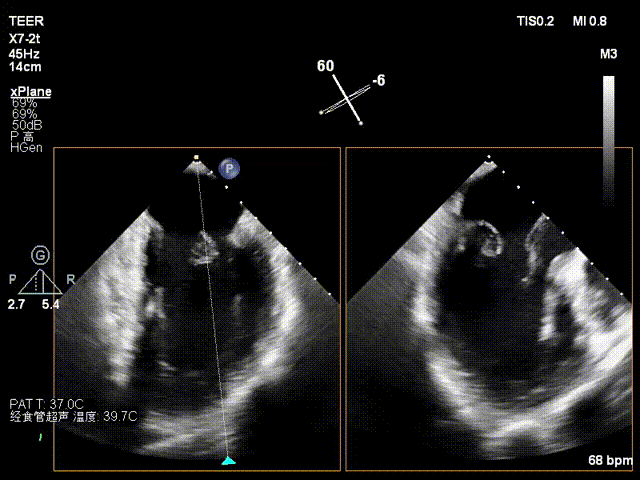

术前影像

X-plane2区

X-plane 1区

X-plane 2区